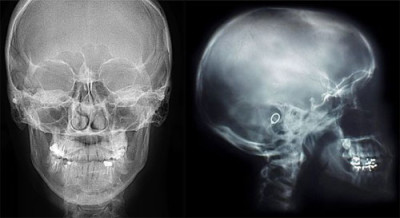

• рентгенРентгенография черепа, в частности, височной кости. На рентгеновском снимке кости холестеатома выглядит как плотная тень, помещенная в округлую полость. Этот метод позволяет достаточно точно определить размеры образования и его нахождение.